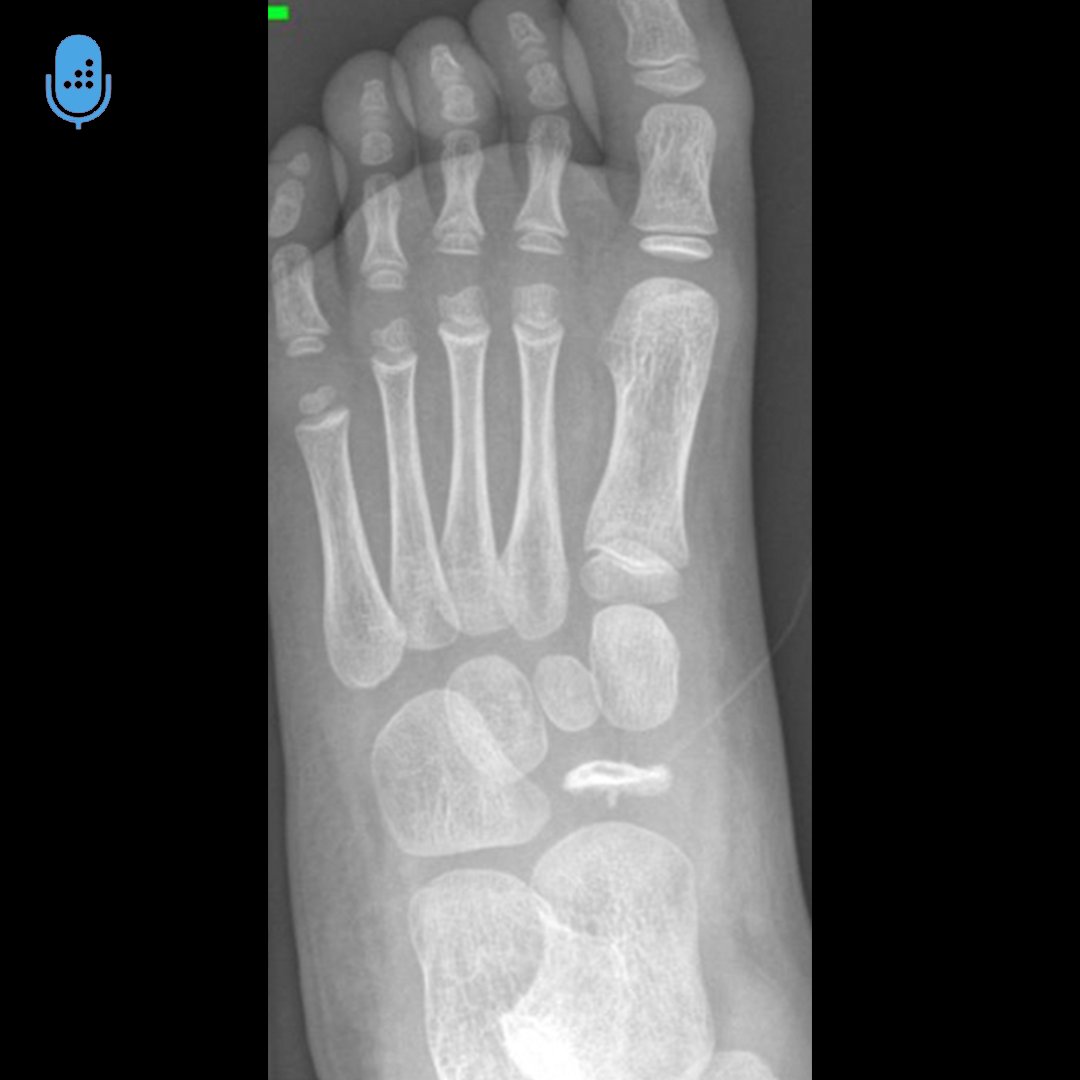

Navicular Bone Fracture Orthobullets. The extensive articular cartilage around the bone limits its blood supply and these anatomic and functional features make the navicular bone vulnerable, so that injuries may have serious. Retrospective radiographic review using the. Acessory navicular is a common idiopathic condition of the foot that presents with an enlargement of the navicular bone. Diagnosis is made with plain radiographs of the foot. To assess injury patterns and outcomes after navicular fractures. Plain radiographs are the best initial test in a suspected navicular fracture. Treatment can be nonoperative or operative depending on fracture displacement, ankle stability, presence of syndesmotic injury, and patient activity demands. The tarsal navicular bone is the keystone of the medial column of the foot, bearing the majority of the load applied to the tarsal complex during. Tarsal navicular fractures are rare fractures of the midfoot that may occur due to trauma or due to repetitive microstress. Fractures of the tarsal navicular bone are most commonly the result of either traumatic injury or undue stress, with the latter having a higher incidence in younger individuals and athletes. Their sensitivity for identifying navicular fracture is low;

The tarsal navicular bone is the keystone of the medial column of the foot, bearing the majority of the load applied to the tarsal complex during. The extensive articular cartilage around the bone limits its blood supply and these anatomic and functional features make the navicular bone vulnerable, so that injuries may have serious. Treatment can be nonoperative or operative depending on fracture displacement, ankle stability, presence of syndesmotic injury, and patient activity demands. Their sensitivity for identifying navicular fracture is low; To assess injury patterns and outcomes after navicular fractures. Acessory navicular is a common idiopathic condition of the foot that presents with an enlargement of the navicular bone. Fractures of the tarsal navicular bone are most commonly the result of either traumatic injury or undue stress, with the latter having a higher incidence in younger individuals and athletes. Diagnosis is made with plain radiographs of the foot. Tarsal navicular fractures are rare fractures of the midfoot that may occur due to trauma or due to repetitive microstress. Retrospective radiographic review using the.